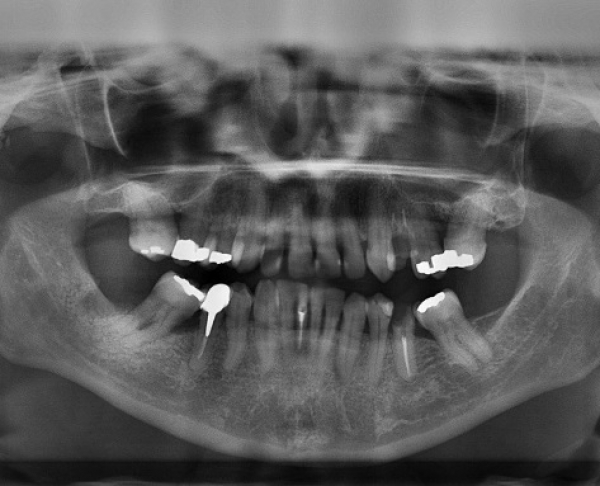

Izpostavljenost organizma živemu srebru že dolgo velja za škodljivo za zdravje ljudi, kar so pokazale že številne raziskave. Živo srebro se med drugim uporablja za zobne zalivke, tako imenovane klasične amalgamske zalivke. Amalgami so zlitine živega srebra in drugih kovin, živo srebro se uporablja zaradi njegovih vezivnih lastnosti in obstojnosti takšnih zalivk.

Raziskava, ki jo je izvedla skupina strokovnjakov z ameriške univerze Georgia, je pokazala, da je raven živega srebra v krvi ljudi, ki imajo v ustih osem amalgamskih zalivk, dvakrat višja kot pri tistih brez zalivk.

Toksičnim učinkom živega srebra niso izpostavljeni le bolniki. Zobozdravstveno osebje je prav tako izpostavljeno hlapom živega srebra vsakič, ko namešča amalgamske zalivke.